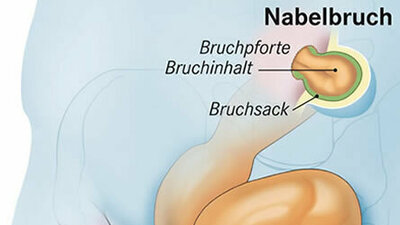

In der Schwangerschaft wölbt sich der Bauch – und manchmal auch der Nabel. Der "Nabel verstreicht", das heißt die Nabelvertiefung verschwindet. Verstreicht er nicht nur, sondern bildet sich eine Art Beule im Nabelbereich, kann ein Nabelbruch dahinterstecken. Dabei handelt es sich um eine Ausstülpung von Gewebe durch eine Schwachstelle oder Lücke in der Bauchwand – die sogenannte Bruchpforte. Ärzte sprechen von einer "Nabelhernie".

Üblicherweise bereitet ein solcher Bruch den werdenden Müttern keine Schmerzen. Tut er jedoch weh oder verfärbt er sich bläulich, sollte man unbedingt zum Arzt gehen: Es könnte sich um eine Einklemmung handeln, bei der sich Darmgewebe in der Bruchpforte verklemmt hat und nicht mehr richtig durchblutet wird.

Dabei handelt es sich um einen Notfall und einen der wenigen Gründe, warum ein Nabelbruch in der Schwangerschaft operiert wird. "Zum Glück ist das aber eine absolute Rarität", sagt Köckerling. "Außer bei der Einklemmung operieren wir eigentlich nur, wenn die Schwangere durch den Nabelbruch Schmerzen hat, die ein Abwarten bis nach der Entbindung unmöglich machen."